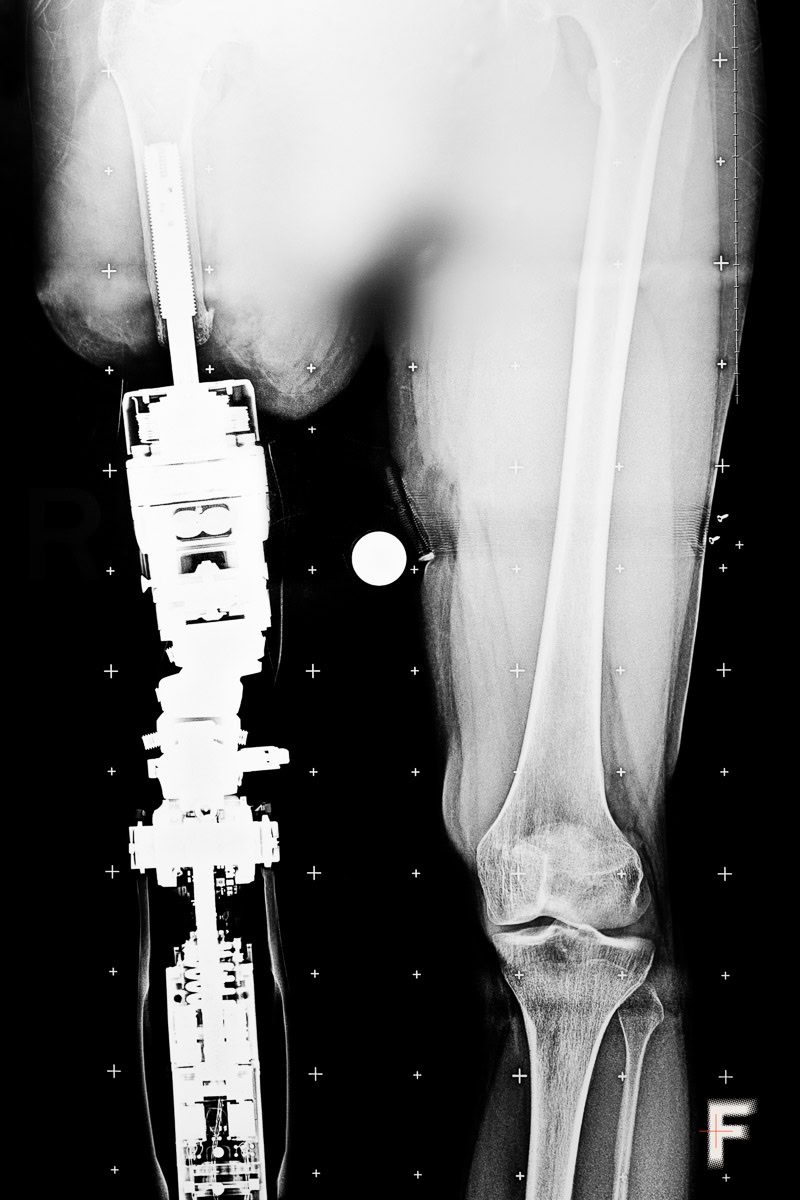

In the first year and a half of the full-scale Russian invasion, the number of amputations in Ukraine reached the scale of World War I. As a result of hostilities and Russian shelling, at least 50,000 Ukrainians have lost limbs, as previously reported by The Wall Street Journal, citing Ottobock, the world’s largest manufacturer of prostheses. About 80% of people with amputations experience pain in the lost limb, and almost all of them feel as if it is still there.

Military serviceman Vadym Sitarchuk underwent a course of ketamine therapy. After being wounded and having both legs amputated, he withdrew into himself: he hardly spoke and avoided communication even with those closest to him. His physical pain was compounded by emotional pain – depression, anxiety, and nightmares.